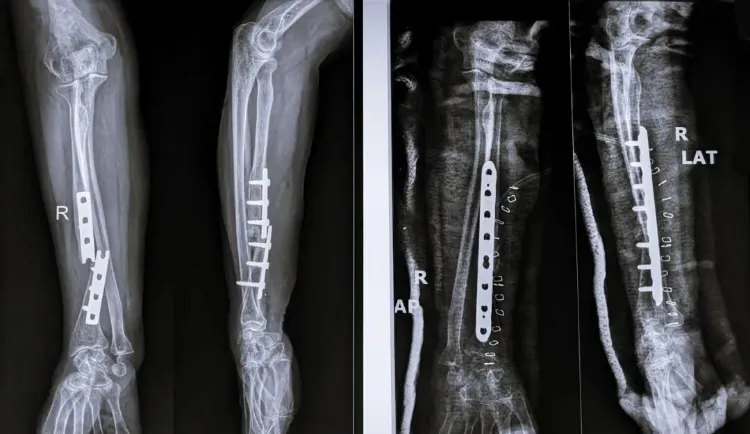

这场技术革新带来的改变是颠覆性的。在一个典型的临床案例中,一位年轻工人因外伤导致手腕粉碎性骨折。传统方案意味着一个大切口、植入钢板螺钉,以及一年后的二次手术。而使用“骨02”,医生仅通过一个2-3厘米的微创切口,注入材料,3分钟内就完成了所有碎骨的精准固定。术后三个月,患者骨折完全愈合,手腕功能恢复如初。

这标志着一种治疗哲学的转变。传统的金属内固定是“刚性固定”,为了稳定,不得不广泛剥离软组织,破坏骨骼的血液供应。而“骨02”是“生物固定”,它精准作用于骨折线,最大限度地保护了周围的生命组织,为身体的自我修复创造了最佳环境。手术时间从几小时缩短到几分钟,创伤更小,出血更少,恢复更快。